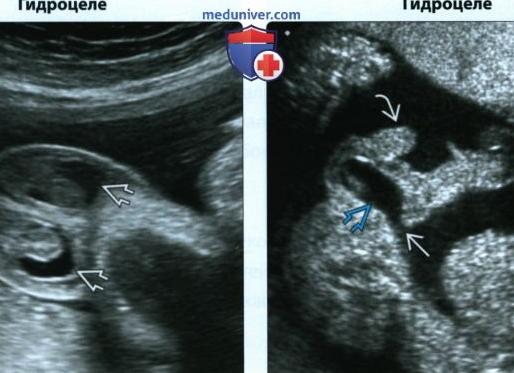

Гидроцеле у плода достаточно частая и обычно несообщаемая находка в заключении ультразвукового исследования. Эхографически гидроцеле проявляется визуализацией эхонегативного пространства в мошонке плода и может быть двусторонним или односторонним.

Различают 2 основных типа гидроцеле: сообщающийся с брюшной полостью и несообщающийся. При несообщающемся типе количество жидкости в мошонке приблизительно одинаковое, размеры и форма мошонки существенно не меняются. Этот тип гидроцеле обычно исчезает спонтанно и не требуетлечения. При сообщающемся типе отмечается увеличение количества жидкости в мошонке при динамическом эхографическом наблюдении, что позволяет заподозрить пахово-мошоночную грыжу.